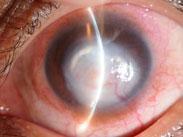

• 銅綠假單胞菌性角膜炎

銅綠假單胞菌性角膜炎(pseudomonaskeratitis)是一種極為嚴重的急性化膿性角膜潰瘍,具有典型革蘭陰性桿菌所引起的環形膿腫的特征,常在極短時間內席卷整個角膜而導致毀滅性...

• 綠膿桿菌性角膜潰瘍

是一種最嚴重的化膿性角膜炎,癥狀劇烈,發展迅速,可于24~48小時內破壞整個角膜,數日內即可失明,必須及時搶救治療,并作好消毒隔離,嚴防交叉感染。...